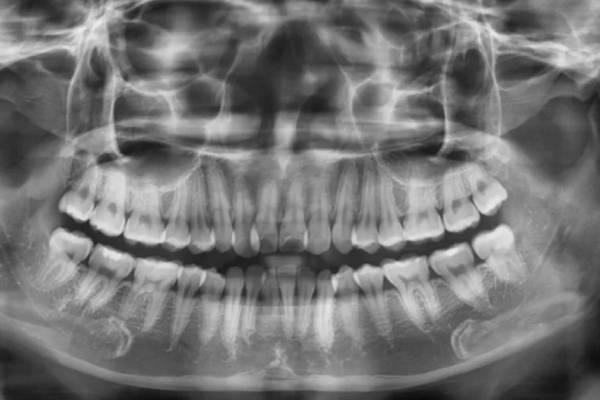

5.1 Bước 1: Thăm khám và tư vấn

Trước tiên, bác sĩ sẽ tiến hành thăm khám cụ thể vùng cần trám và tiến hàng chụp X-quang cho người bệnh. Sau đó dựa vào kết quả kiểm tra để lên phác đồ điều trị phù hợp với từng bệnh nhân.